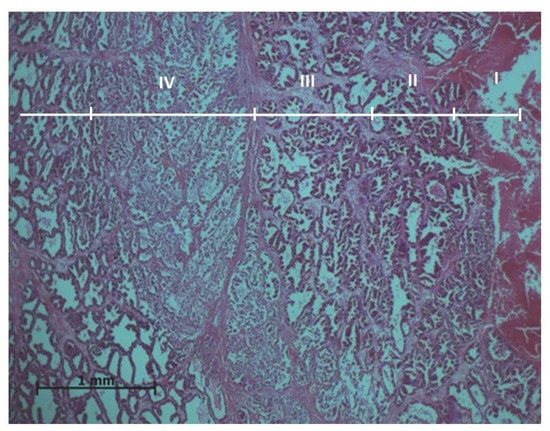

Experimental results showed that ablation effects on the prostate tissues vary going further from the active electrode. Thus, the histopathological evaluation of the prostate samples resulted in four exposure zones (Figure 1).

Figure 1.

General histologic image of the prostate after ablation: I—ablation site; II—application zone; III—necrosis zone; IV—transition zone. Microtome-cut sections of prostate samples were stained with hematoxylin and eosin.